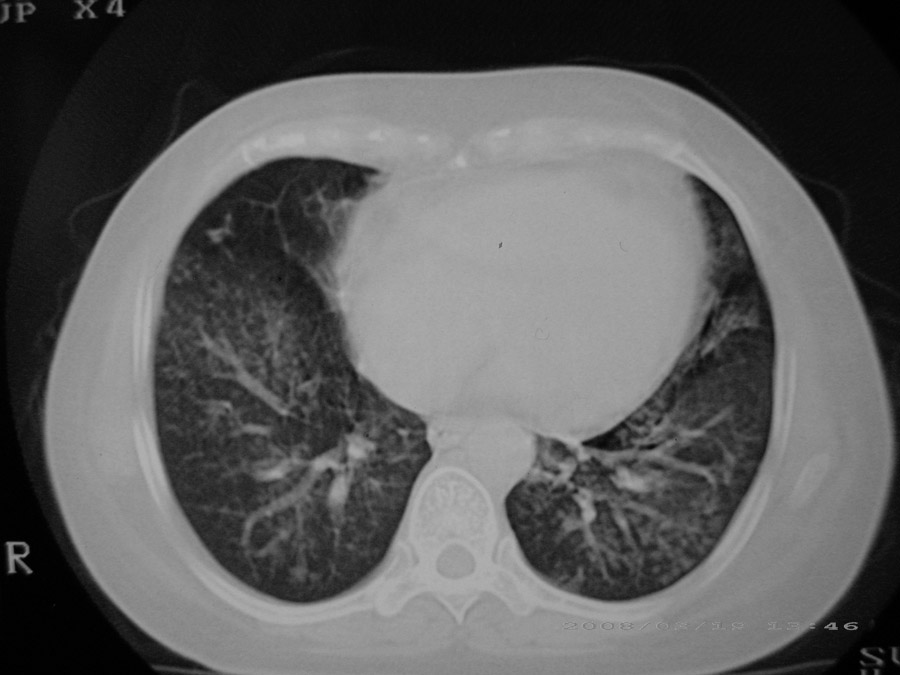

粟粒性结核

密漫性沿纹理走行小结节影;有间质纤维化;可考虑尘肺;以图而论

血行播散性肺结核

双肺网状结构,小叶间质结节状增厚,考虑结节病

综合大家意见,结核、结节病、肺泡细胞癌均有可能,间质性肺炎暂不考虑,病灶纠集不明显,纵隔未见钙化淋巴结,尘肺可能性不大,但还是要密切结合临床诊断。

今天重新仔细看了看,矽肺确实不能除外,病灶主要表现为间质结节及纤维化。好好问问病史吧。